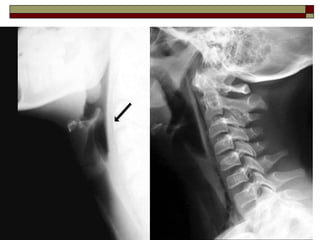

 Rx Cervical:

 No es útil para evaluar lesiones vasculares o

relacionada a tejido blando.

 Puede mostrar hematomas de tejidos blandos

icnluyendo el espacio prevertebral

 Evalúa enfisema, fracturas, desplazamiento de

la tráquea y presencia de cuerpo extraño